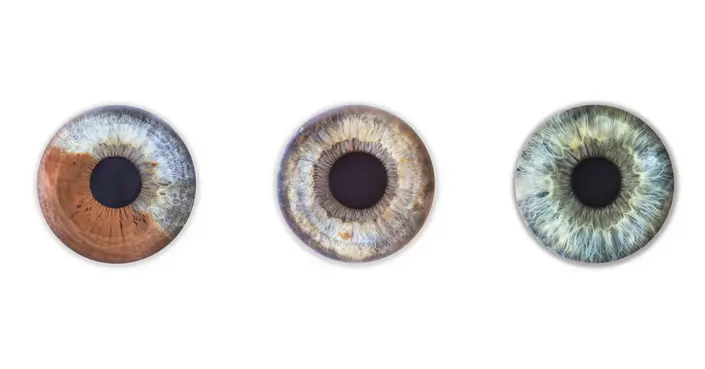

القزحية هي الغشاء الملون والحلقة العضلية الموجودة في الجزء الأمامي من العين، وتحديدًا خلف القرنية وأمام العدسة. لونها المميز هو ما يمنح العيون ألوانها المختلفة، سواء كانت بنية، زرقاء، خضراء، أو عسلية، وذلك بفضل صبغة الميلانين التي تحتوي عليها.

يعتمد لون القزحية على كمية صبغة الميلانين. في بعض الحالات، يحدث ما يُعرف بتغاير لون القزحيتين، حيث يختلف لون إحدى العينين عن الأخرى تمامًا، أو تظهر عدة ألوان ضمن القزحية الواحدة. غالبًا ما تكون هذه الحالة غير ضارة ولا تؤثر على البصر.

يمكن تصنيف تغاير لون القزحيتين إلى ثلاثة أنواع رئيسية:

- تغاير اللون الكامل: تكون كل عين بلون مختلف تمامًا، على سبيل المثال، عين زرقاء والأخرى بنية.

- تغاير اللون القطعي: وجود عدة ألوان متميزة داخل قزحية العين نفسها.

- تغاير اللون المركزي: يختلف لون حافة القزحية المحيطة بالبؤبؤ عن لون باقي القزحية.